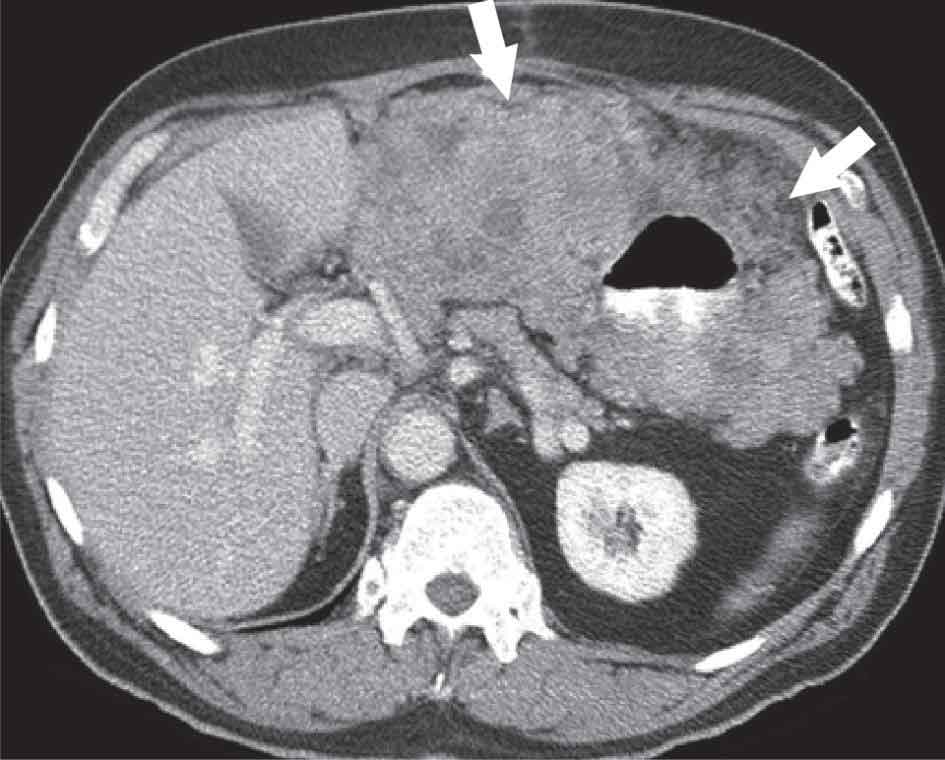

الشكل (1) الساركومة المنسجة الليفية

الشكل (5)

أورام السدى المعدية المعوية

GIST

1- أورام السدى المعدية المعوية:GIST

هي من الأمراض النادرة تنشأ بسبب تفعيل طفرات من الجين المحرض لتشكيل الورم «كيت KIT» وهي مستقبلة التيروزين كيناز، يمكن كشف هذه الأورام وتأكيد تشخيصها بالتلوينات المناعية. ومن السبق الطبي الكبير في العصر الحالي كشف الأيماتينيب imatinib (Glivec) وهو مركب دوائي مثبط مباشر للتيروزين كيناز يعطل الخلايا ويؤدي إلى موتها، وهو معالجة فعالة جداً وملطفة لهذا المرض حين انتشاره أو بشكله الموضع غير القابل للاستئصال الكامل، كما أن الدواء فعال أيضاً بعد استئصال الورم كاملاً بوصفه معالجة مساعدة. وهناك علاج بديل للمرضى المعندين وهو دواء سونيتينيب sunitinib وهو مثبط للتيروزين كيناز متعدد الأهداف.